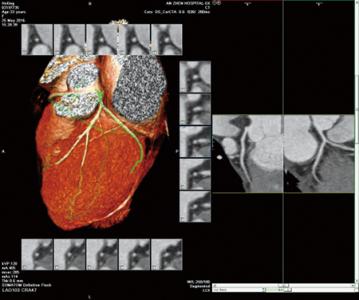

冠状动脉CTA检查是一项用于检查动脉血管是否正常的辅助检查,通过注射造影剂做血管造影可得CT血管造影,用于判断大动脉炎、动脉硬化闭塞症、主动脉瘤及夹层 等病症,用于帮助临床诊断。是冠心病早期筛查的首选,冠脉PCI、搭桥随访观察,冠脉钙化精确测定的最优选择。